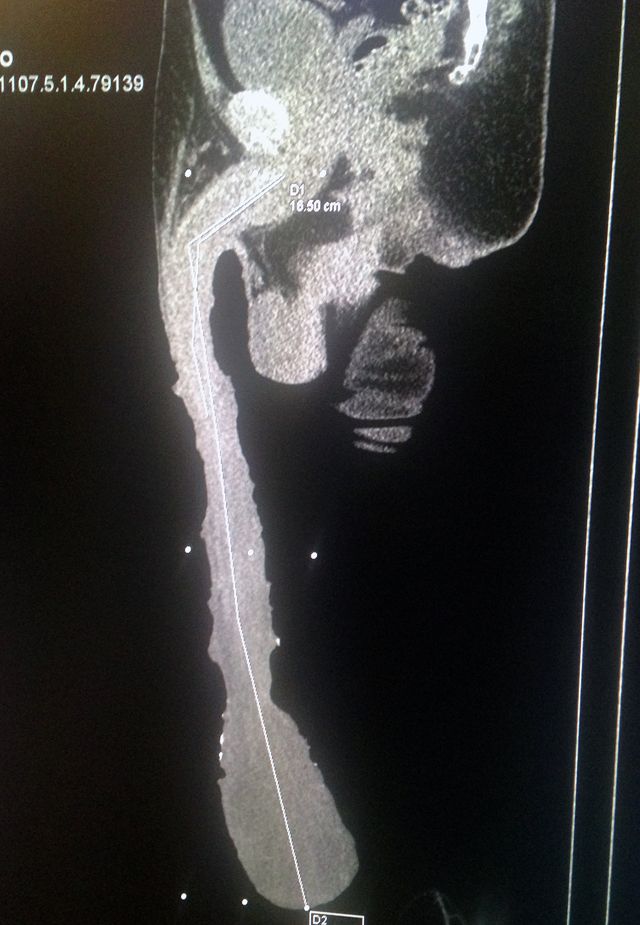

)の最新画像。48cm(内33cmは皮)のチンコを持つロベルトさんがズボンを履いたらこうなる・・・他、X線撮影、X線断層撮影など。[9]images

※ X線断層撮影